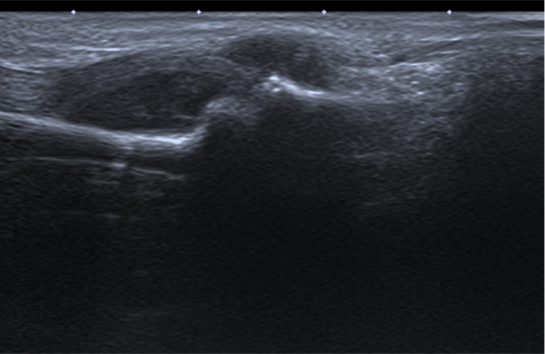

Se solicitan pruebas de imagen: RX, ECO, RM.

1. ¿Como describirías los hallazgos en RX y ecografía?

- A. Tumoración de partes blandas que asocia erosión ósea adyacente.

- B. Tumoración de partes blandas sin erosión ósea adyacente.

- C. Derrame articular.

- D. Erosiones articulares con componente de partes blandas asociado.

- E. Ninguna de las respuestas es correcta.